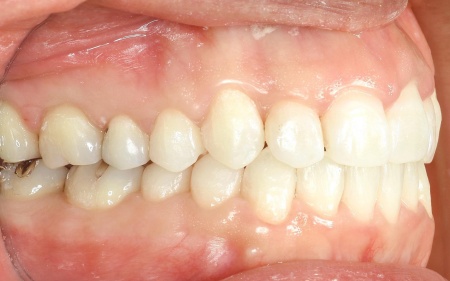

40代女性 デコボコの歯並びと開咬をマウスピース矯正と舌のトレーニングで改善した症例

「奥歯で噛むと上下前歯が触れ合わないので、噛み合わせを治したい。また、歯並びがデコボコしているのも気になる」とご相談いただきました。

拝見したところ、奥歯で噛んだ際に上下の前歯が触れ合わず、隙間ができている状態でした。

これは開咬(かいこう)と呼ばれ、前歯で食べ物を噛み切るのが難しい噛み合わせです。

加えて全体的に歯が重なり合ってデコボコに生えており、歯磨きがしにくく、審美性にも悪影響がでています。